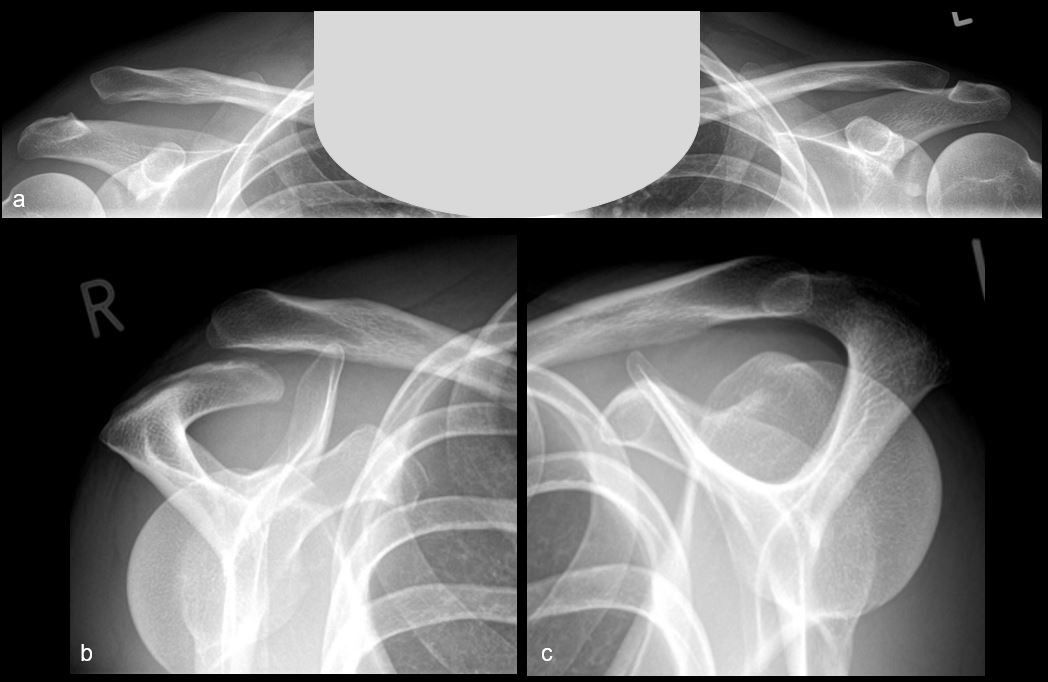

Technique Innovations dans la reconstruction de l’articulation acromioclaviculaire au moyen d’implants à profil bas , Marvin Minkus Charité-Universitaetsmedizin Berlin, Allemagne - , Nina Maziak Charité-Universitaetsmedizin Berlin, Allemagne - , Philipp Moroder Charité-Universitaetsmedizin Berlin, Allemagne - , Markus Scheibel Charité-Universitaetsmedizin Berlin, Allemagne - N°291 - Février 2020 ● 9 min de lecture